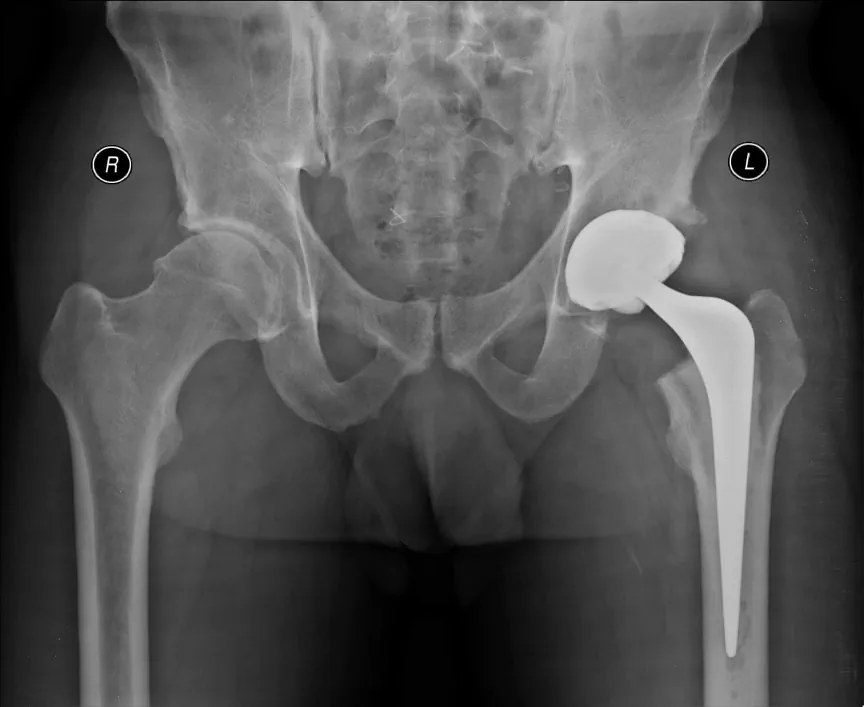

Chapa de raio-X de quadril com prótese

Prótese ou artroplastia do quadril é a substituição da articulação do paciente por uma artificial.

Os componentes da prótese são feitos de materiais diversos, até mesmo em uma só prótese. A parte do fêmur pode ser feita de ligas de titânio ou de cromo-cobalto. A cabeça pode ser feita de metal (normalmente cromo-cobalto) ou cerâmica. A parte da bacia pode ser feita de polietileno (um plástico muito resistente) ou cerâmica.

As próteses podem ser fixadas no osso com cimento ortopédico (um polímero chamado poli metil meta acrilato ou PMMA) ou podem ser integradas ao osso quando este cresce para dentro de poros na prótese.